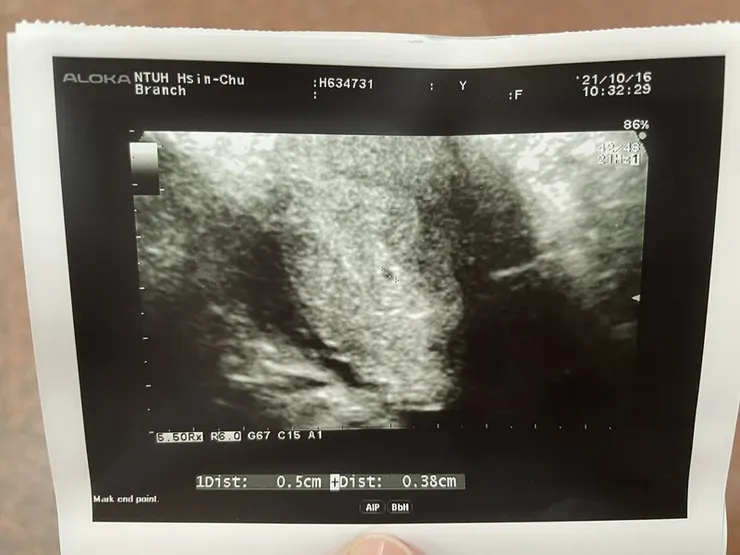

【第5周~第一張超音波照片】

驗完第一隻驗孕棒後,立馬預約新竹台大婦產科做檢查! 就這樣GET人生中第一張寶寶超音波照片!

不過也太小一顆了吧~~~ 好難想像之後會變一個寶寶@@

醫生說下周再來看胚囊有沒有按時長大~